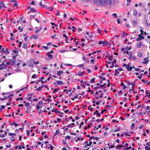

Histopathology. Typically, a dense perivascular infiltrate composed largely of neutrophils is seen assuming a bandlike distribution throughout the papillary dermis . Some of the neutrophils may show nuclear fragmentation (leukocytoclasis). In addition, the infiltrate may contain scattered lymphocytes and histiocytes and occasional eosinophils. The density of the infiltrate varies and may be limited in a small proportion of cases. Vasodilation and swelling of endothelium with moderate erythrocyte extravasation and prominent edema of the upper dermis are characteristic. In some instances, subepidermal blister formation may result. Extensive vascular damage is not a feature of Sweet’s syndrome. The histologic appearance varies depending on the stage of the process. In later stages, lymphocytes and histiocytes may predominate. Sweet’s-like neutrophilic dermatoses often show a similar histologic picture. However, the reaction pattern may on occasion be quite different, for instance, manifesting as deep subcutaneous localized suppurative panniculitis. The infiltrate of Sweet’s syndrome is not characteristic enough to exclude infection on histologic findings alone. As always, to arrive at the correct interpretation of a neutrophilic infiltrate, cultures need to be obtained and special stains need to be performed to exclude an infectious etiology. |